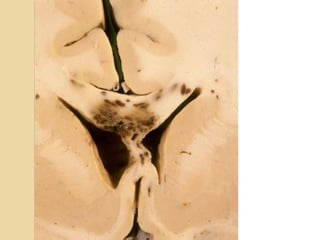

BRAINSTEM INJURYBRAINSTEM INJURY Bydirect or indirect forces Most commonly associated with DAI Involves the dorsolateral midbrain and upper pons and is usually hemorrhagic Duret hemorrhage is an example of indirect damage: tearing of the pontine perforators leading to hemorrhage in the setting transtentorial herniation <20% of brainstem lesions are seen on CT

BRAINSTEM INJURYBRAINSTEM INJURY

By direct or indirect forces

Most commonly associated with DAI

Involves the dorsolateral midbrain and upper

pons and is usually hemorrhagic

Duret hemorrhage is an example of indirect

damage: tearing of the pontine perforators

leading to hemorrhage in the setting

transtentorial herniation

<20% of brainstem lesions are seen on CT